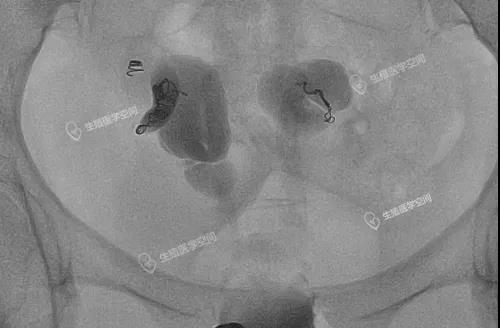

图9:双侧输卵管均栓塞一个弹簧圈

双侧输卵管积水在移植前我做的双侧输卵管均栓塞单个弹簧圈,移植怀孕后她发给我的怀双胎的信息。